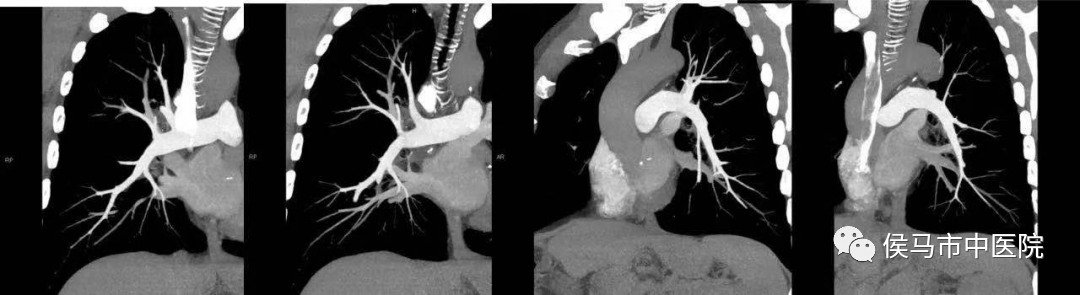

2、肺动脉CT血管造影(CTA)

肺动脉CTA是诊断肺动脉血栓栓塞的重要标准、也是先天性肺动脉发育异常、原发性或原因不明的肺动脉高压及纵隔肿瘤和大血管病变的主要依据,特别是诊断肺动脉血管有无血栓,以及有无血管硬化,准确性特别高,是一种评价肺动脉血管的无创性检查方法。